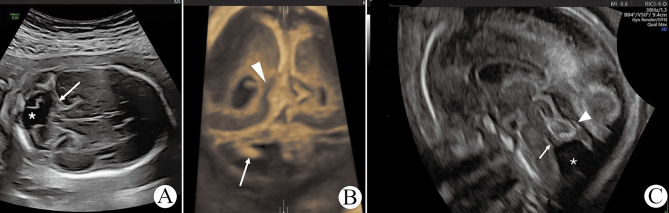

Prenatal Diagnosis of Okur-Chung Syndrome: Ultrasound Findings and Implications of CSNK2A1 and KCNQ5 Variants.

Okur-Chung综合征的产前诊断:CSNK2A1和KCNQ5变异的超声结果和意义